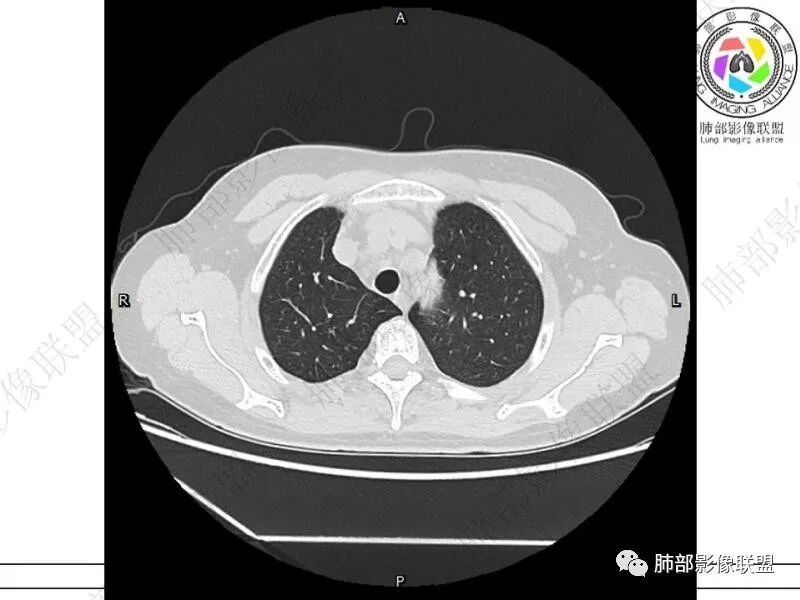

摘星空竹子:两肺胸膜下多发实性结节、磨玻璃影及实变影,短期复查病变有所进展,考虑感染性病变,隐球菌可能,患者有右半结肠癌手术史,转移不能除外。

简单:双肺及胸膜下多发小结节,双下肺胸膜下宽基底团块影,短期内病灶进展考虑炎性病变,隐球?患者ca术后,双肺小结节随诊除外转移

丽:双肺下叶胸膜下多发片状高密度影,边缘模糊不清,内可见支气管穿行,病变长轴平行于胸膜,考虑感染性病变,隐球菌

媛:肠癌术后,免疫力低下。两肺胸膜下结节及实变影,实变影长轴平行于胸膜,密度均匀,边界偏清,周围有晕征,短期复查进展,虽隐球菌荚膜抗原检测阴性,还是考虑隐球菌,鉴别OP

谢加平:结肠癌术后史,两肺胸膜下多发结节及斑块实变病灶,实边边界平直征(亚急性和慢性病变过程),双肺下叶后基底段胸膜下为甚,与胸膜平行特点,见支气管充气征,边缘模糊的GG0,首诊2022年11月18日肺部CT,与治疗11月28日对比,病灶未吸收,双肺下叶胸膜下病灶有侧向融合特点,综合分析符合炎性肉芽肿,隐球菌感染。

良孑:两肺胸膜下多发相类似结节,部分结节有晕及晕中软毛刺,部分结节侧向融合,长轴与胸膜平行,结节边缘可见刀切征,右半结肠癌术后免疫力低下,综合考虑支持隐球菌

老年女性,结肠癌术后。两下肺胸膜下为主片状实变,右下肺短期复查融合且病灶长轴平行于胸膜,实变内可见支气管充气征,边缘磨玻璃晕,另两肺内胸膜下散在数枚小结节状、楔形实性灶。考虑感染性病变,隐球菌可能,鉴别肺转移。

2.影像特征:双肺胸膜下多发实性结节、磨玻璃影及实变影,胸膜下优势分布、晕征、胸膜下脂肪间隙存在,部分病灶边界平直征,有侧向融合趋势。